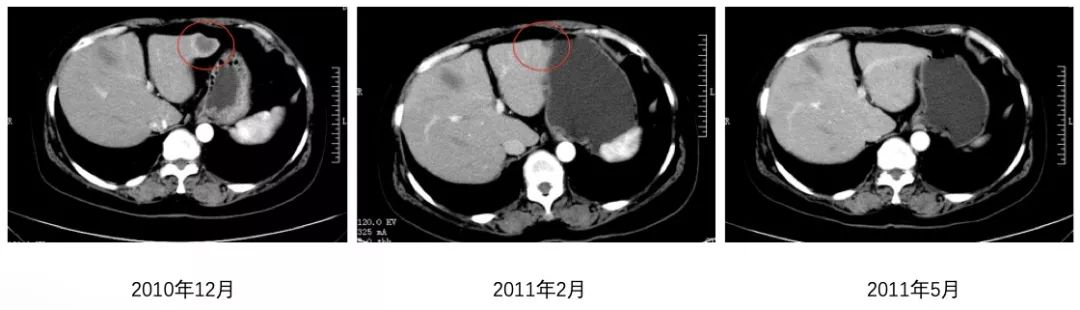

2011年2月2周期治疗后复查腹部CT示:肝转移灶较前对比明显缩小,综合疗效评价为部分缓解(partial response,PR)。4周期治疗后于2011年5月复查腹部CT示:肝脏未见转移灶,其综合疗效评价为完全缓解(complete response,CR)。后患者因不能耐受化疗的毒副作用,仅采用曲妥珠单抗维持治疗,用药期间定期复查,截至目前未见明显转移与复发征象,其无进展生存期(progression-free survival, PFS)为103个月。

图1 患者腹部CT肝脏病灶变化